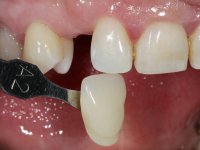

Female patient, 43 years old, non-smoker. Showed an edentulous space in the upper right canine area, resulting from tooth 1.3 impaction. The space had a mesio-distal diameter reduced to the normal size of the upper canine. This is consistent with the presence in the arch of the deciduous canine up to two years ago). Orthopantomography allows clearly view of tooth 1.3 impaction.The patient has a thick gingival phenotype and tolerable oral hygiene.

The proposed treatment results from the limitations imposed by the patient, who refused an orthodontical pull of the canine into the edntulous space, and was unwilling to extract the impacted canine and place an implant in the zone of 1.3. Thus, the confection of a Maryland Bridge was proposed, with a Zr infrastructure and two retainers. The mesial retainer would be bonded to the palatal face of the tooth 1.2 and the distal retainer was to be bonded to the palatal wall of tooth 1.4.

To define the dental zone to be covered by the Maryland bridge retainers, the patient was asked to perform maximum intercuspidation movements, and the contact points were marked with articular paper. Tooth preparation of the interproximal surfaces was made, to create a prosthetic insertion axis. It was sought that the mesio-distal diameter at the incisal level was equal to the diameter mesio-distal at the cervical level, that is to say, the interproximal walls were parallelized. Tooth preparation was done with fine grain diamond drills, and later polishing was done with abrasive discs. Color information was collected even before confection of the impression, to avoid dehydration of the arcade. Definitive impression was made using wash technique impression with silicone of heavy and regular consistency, both with fast setting, and a working plaster model was prepared in the lab. A laboratory scanner was used to scan the working model, and later, the infrastructure for the Maryland bridge was made using a CAD-CAM process. Ceramic was placed on this subframe. A ceramic adhesive was applied to the internal surface of the wings and connectors, which would enable bonding to the adjacent teeth. The adhesive bridge was bonded in the mouth following the conventional bonding technique. After bonding, the protrusion and laterality movements were carefully checked to avoid undesirable contacts.